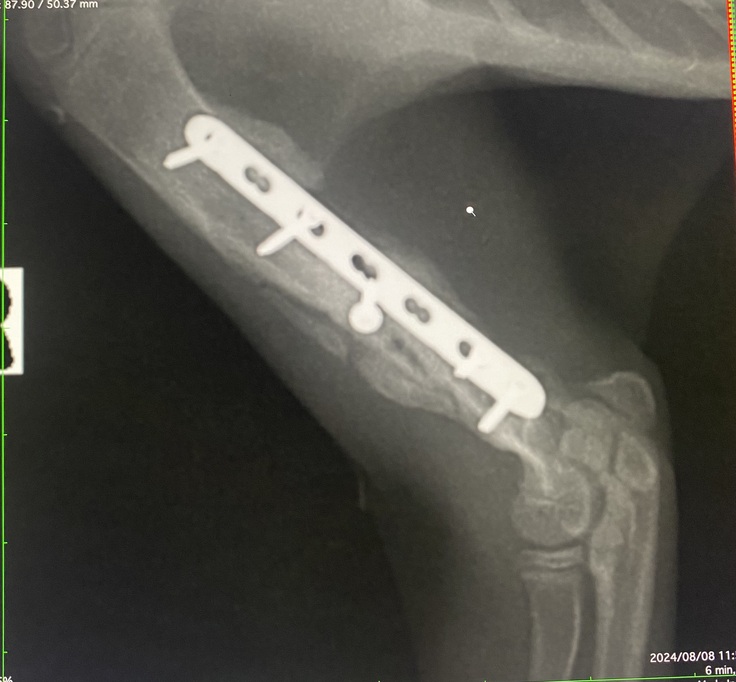

【右上腕 術後】

【本日】こちらはまだ隙間があります。